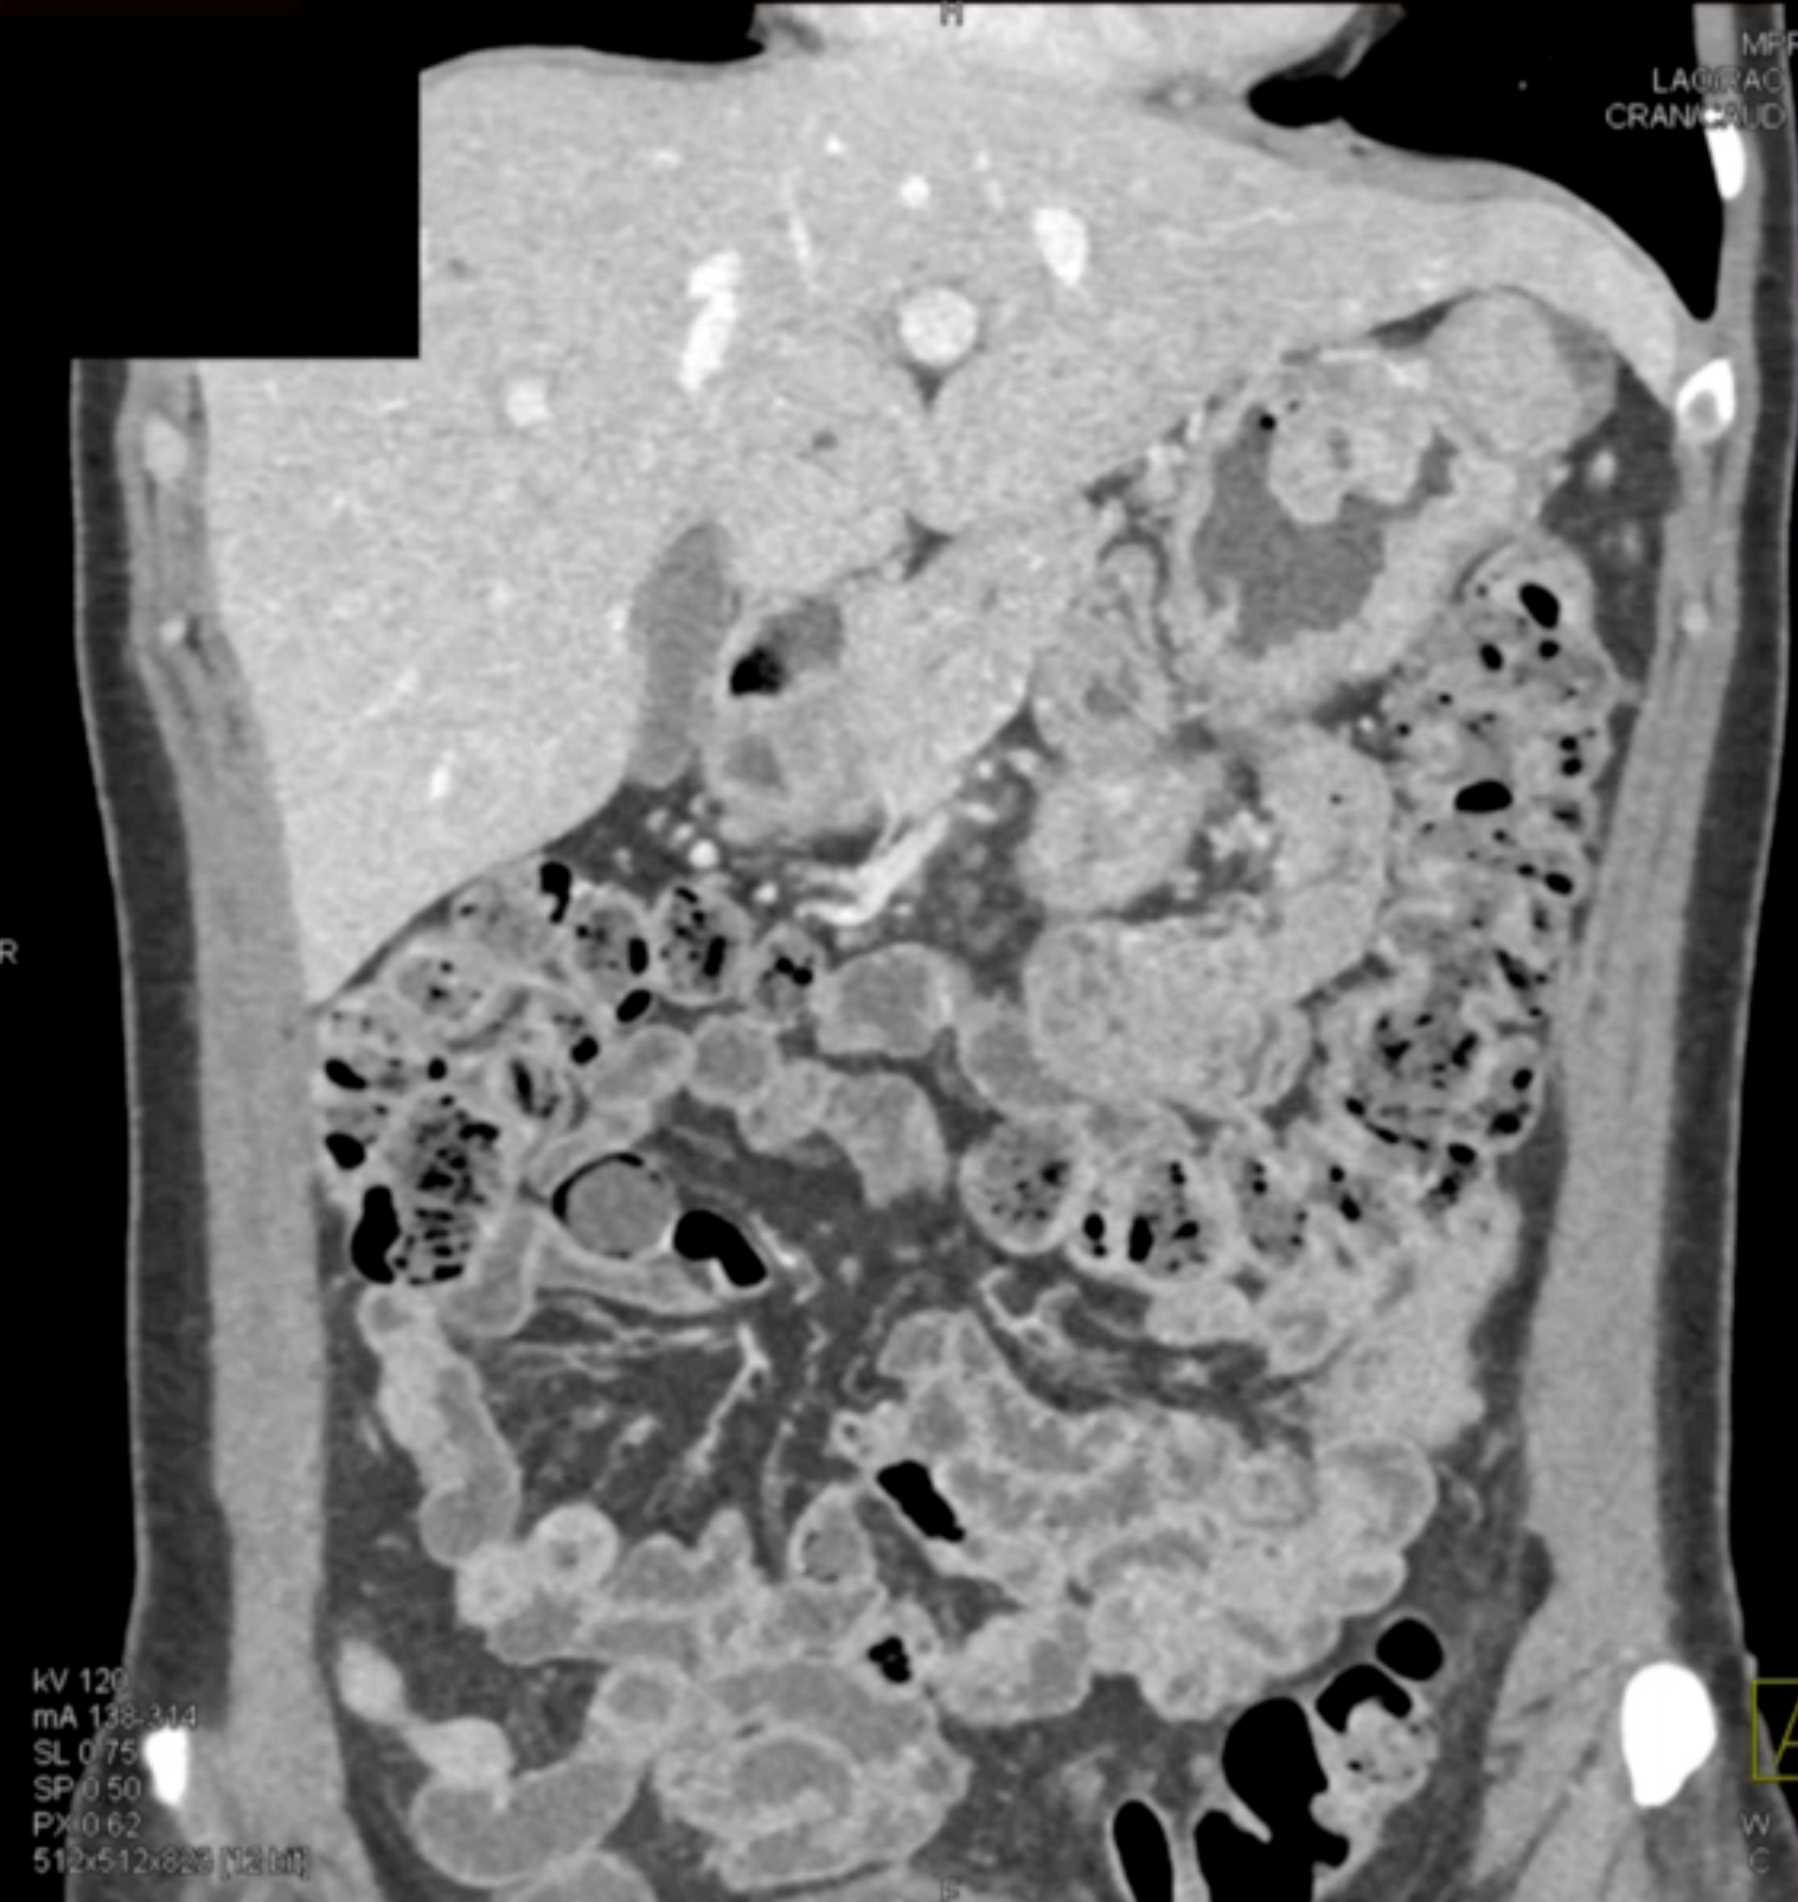

Multiple Gastric GIST Tumors with Spread to Nodes (Carney-Stratakis Syndrome)